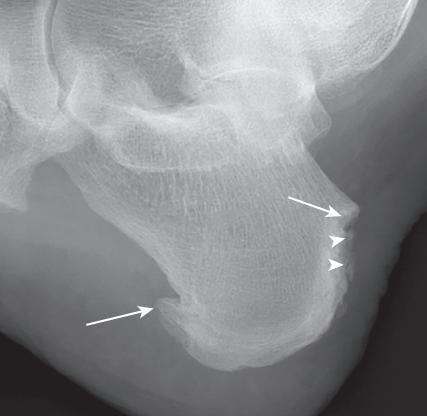

附着点炎;例如,跟腱、足底腱膜和骨盆骨的附着点炎(肌腱、韧带和滑膜附着于骨的部位炎症)。腱鞘炎;例如手部屈肌腱、尺侧腕伸肌或其他部位的腱鞘炎;

图11,跟腱的X光片表现,注意附着点有新骨形成